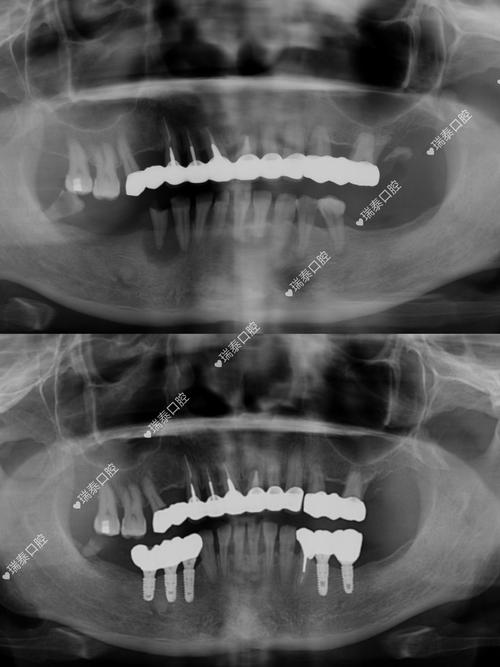

种植牙相当于在牙槽骨中“打桩”,牙槽骨的高度、宽度、密度直接决定种植体能否稳定植入和长期使用,普通X光片(如根尖片、曲面断层片)虽能显示骨大致情况,但存在明显局限性:它是二维重叠影像,无法准确测量骨的垂直高度和水平宽度,尤其对后牙区(如下颌后牙、上颌后牙)的骨量评估误差较大,可能因角度偏差导致实际骨量比预估更少。

而CT(口腔种植常用锥形束CT,简称CBCT)能生成三维立体图像,可精确测量牙槽骨的骨高度(如种植区距离上颌窦底、下颌神经管的距离)、骨宽度(是否足够容纳种植体直径)、骨密度(骨密度过低会影响种植体骨结合),若上颌后牙区牙槽骨高度不足5mm,种植体可能穿入上颌窦,引发感染或种植体失败;若下颌骨宽度不足5mm,植入种植体时可能损伤下牙槽神经,导致下唇麻木,CT能清晰显示这些关键数据,帮助医生判断是否需要植骨、骨增量,或选择更短的种植体,避免盲目手术。

相比之下,普通X光片无法提供角度和三维位置信息,医生仅凭经验设计方案,可能导致种植体位置偏差,影响修复体的美观和功能(如种植体倾斜导致假牙咬合异常)。